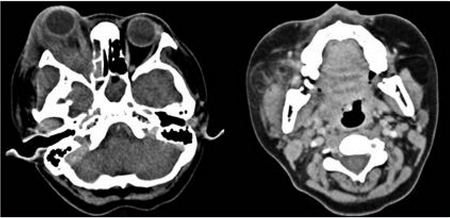

La ultrasonografía ocular reportó una lesión heterogénea que ejercía compresión y desplazamiento en sentido anterior del globo ocular derecho, y datos de inflamación de tejidos blandos (Figura 1). La tomografía computada describió la lesión como heterogénea e identificó datos de sinusitis y proptosis (Figura 2). Por resonancia magnética se reportó la misma lesión con aspecto heterogéneo de 5.5 ' 2.5 cm en sus diámetros mayores, que involucró tejidos musculares y con efecto de masa sobre estructuras orbitarias. No se observó extensión intracraneal, a cavidades paranasales ni al seno cavernoso (Figura 3). Ante una proptosis de rápida evolución y sospecha de probable rabdomiosarcoma se realizó biopsia transconjuntival de lesión intraconal y tejido peri-orbitario. Las preparaciones histológicas de la lesión intraconal y de la grasa orbitaria mostraron tejidos blandos con un proceso inflamatorio, necrótico con vasculitis de vasos de pequeño calibre con afección ocasional a vasos arteriales y venosos de mayor calibre. La vasculitis fue a expensas de linfocitos e histiocitos con trombosis aislada y algunos granulomas mal constituidos. El proceso inflamatorio estaba constituido por linfocitos, histiocitos, células plasmáticas y en una zona se mezclan con numerosos neutrófilos con cariorexis; la necrosis fue isquémica. Se realizaron diversas tinciones de histoquímica convencional e inmunohistoquímica para descartar neoplasia linfoide maligna o proceso infeccioso granulomatoso como micobacterias u hongos. La glándula lagrimal mostró afección por el proceso inflamatorio, la necrosis isquémica y la propia vasculitis. El diagnóstico fue de: granulomatosis de Wegener (Figura 4).

Figura 2 Tomografía axial computada. Se observa lesión lobulada de bordes mal delimitados en región superolateral de la órbita, de 53 × 23 × 38 mm en sus ejes anteroposterior, transverso y craneocaudal, respectivamente. Reforzamiento heterogéneo, en promedio de 50 UH, con componente intra- y extraconal lateral. Pobre interfase entre la lesión nervio óptico ipsilateral, así como con el músculo recto inferior. Las paredes de la órbita se encontraron respetadas, sin alteraciones en fosas temporales. Incremento de la densidad de los tejidos blandos palpebrales tanto superiores como inferiores, engrosamiento mucoso en senos maxilares y esfenoidal izquierdo con presencia de imágenes polipoideas, de hasta 50 UH. UH: unidades Hunsfield.

Figura 5 Tomografía axial computada. Se observa desplazamiento anterior del globo ocular, aumento de volumen y densidad de tejidos blandos de la región periorbitaria derecha con engrosamiento generalizado de los músculos intraconales de diámetro irregular y reforzamiento heterogéneo a expensas de áreas de hipodensidad en el músculo recto lateral. Además se observó ocupación generalizada de senos paranasales con predominio de las celdillas etmoidales del lado derecho y seno esfenoidal izquierdo. Los componentes óseos de los senos paranasales maxilar y celdillas etmoidales del lado derecho, así como el piso de la órbita ipsilateral, se encontraron adelgazados y con esclerosis. Se observa aumento de volumen y densidad heterogénea a nivel de glándula parótida derecha y tejido circundante.